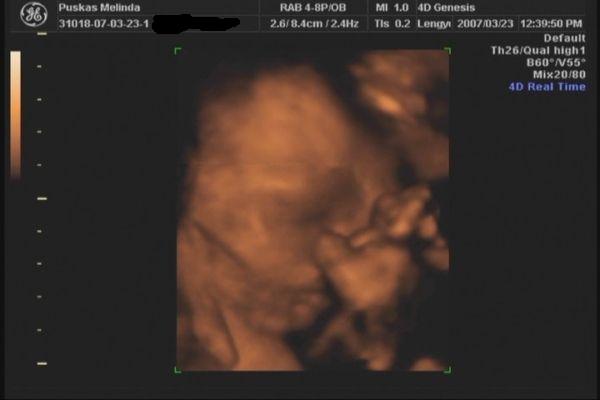

Tegnap voltunk 4D-n. gyönyörű egészséges 31 dekás kislány. :D A Lara Boglárka nevet kapja tőlünk. :) egy kép róla meg egy a pocakról. :)

Kép Kép